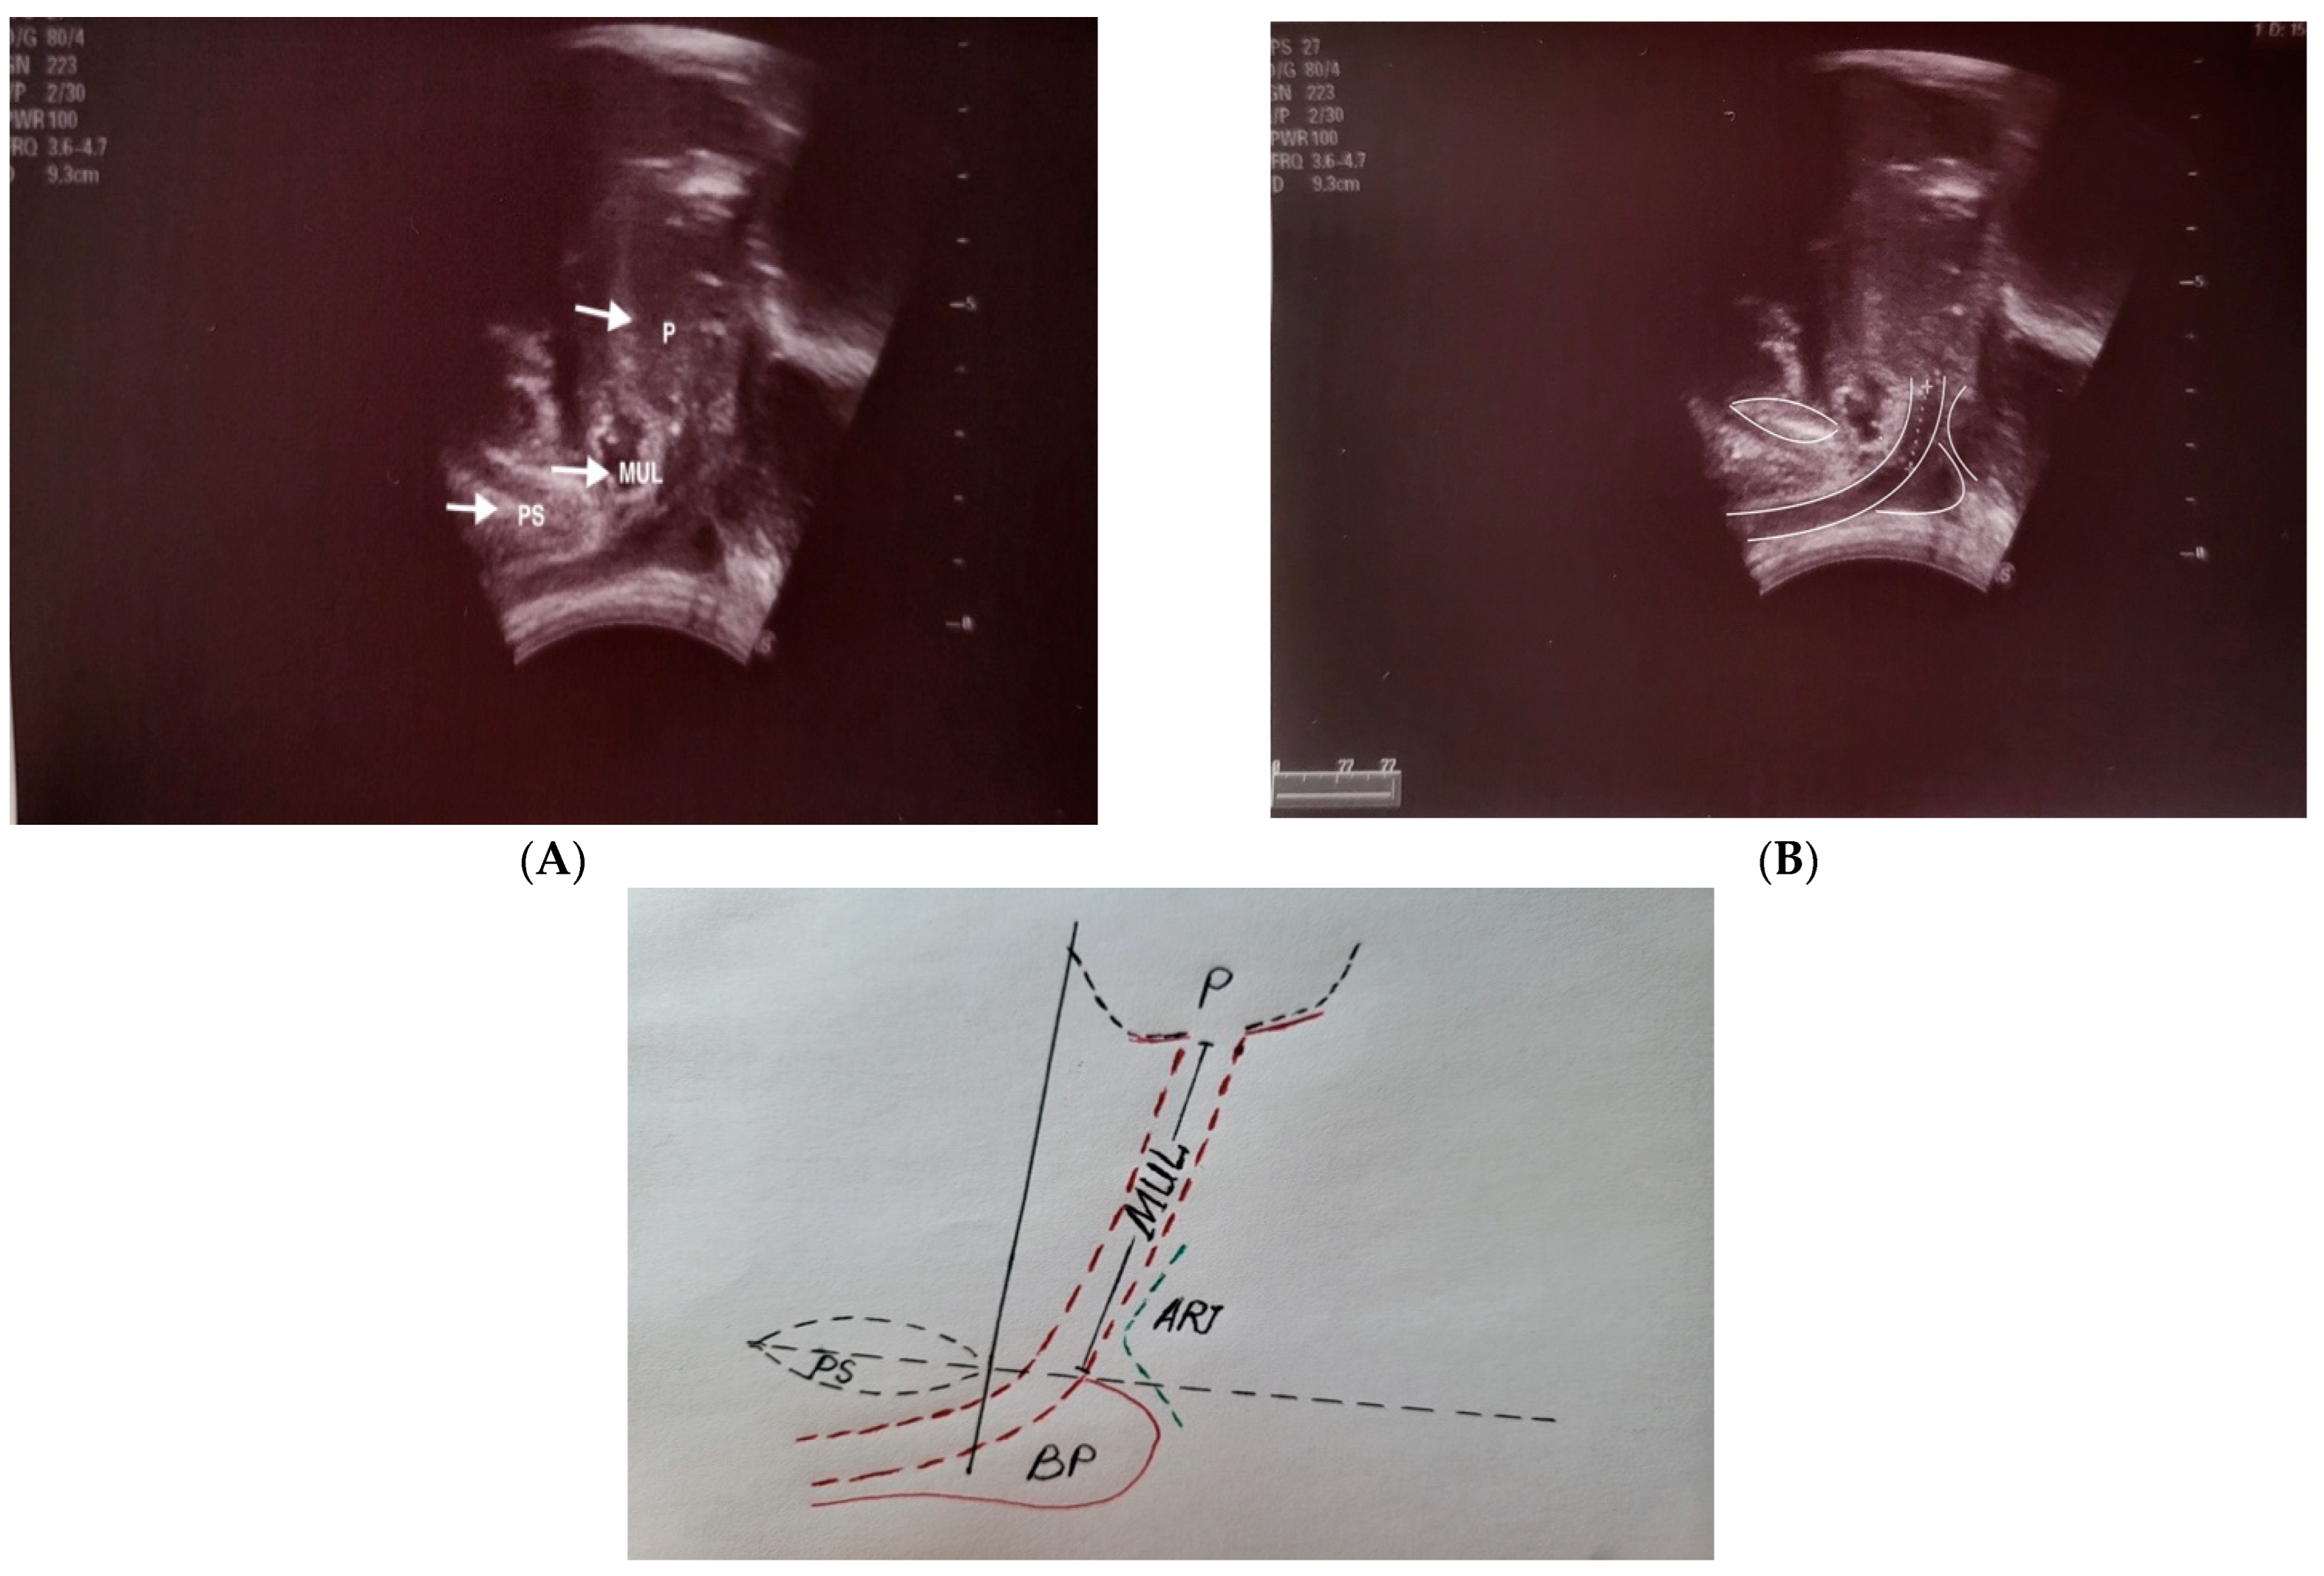

2.2. Transperineal Ultrasound (TPUS)

2.3. Measurement